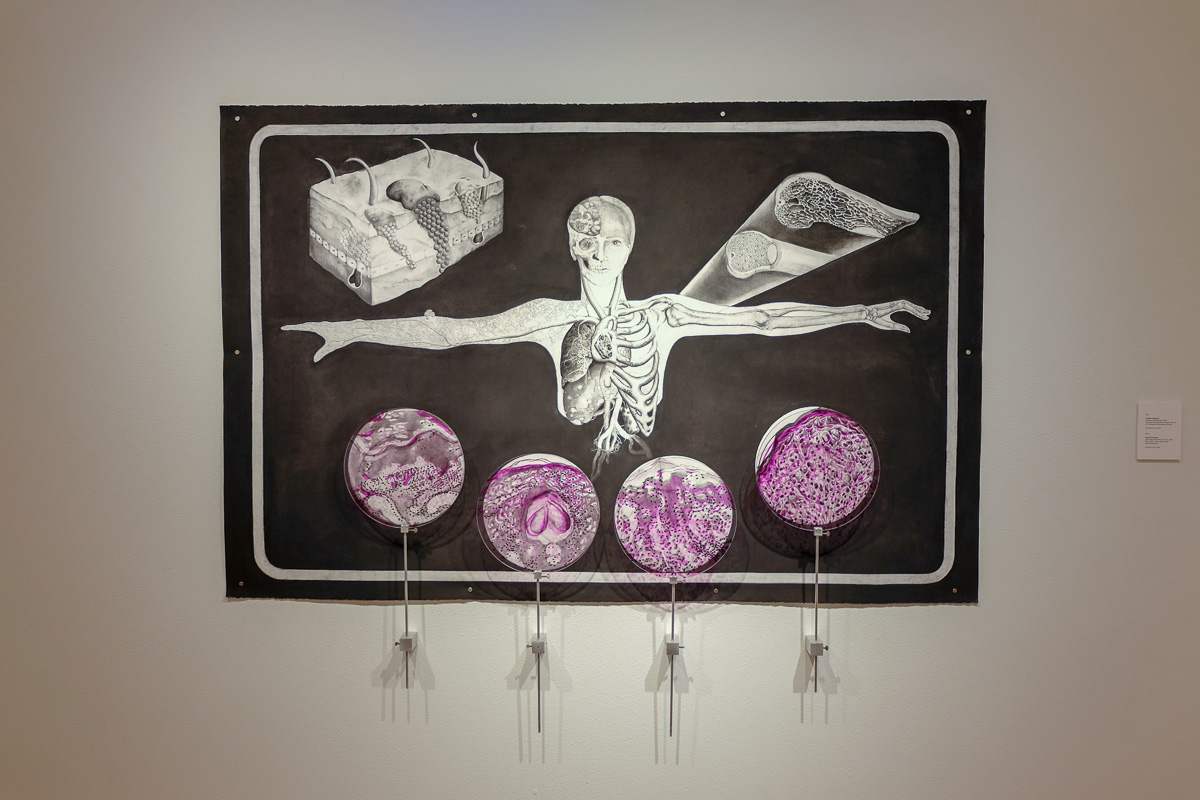

Visualizing Melanoma

Charcoal and graphite on paper with ink on Plexiglas and aluminum mounts

From Visual Pathology: a collaboration with Galveston Art Center and the Department of Pathology at the University of Texas Medical Branch (UTMB).

Image by Roxann Grover

Image by Roxann Grover